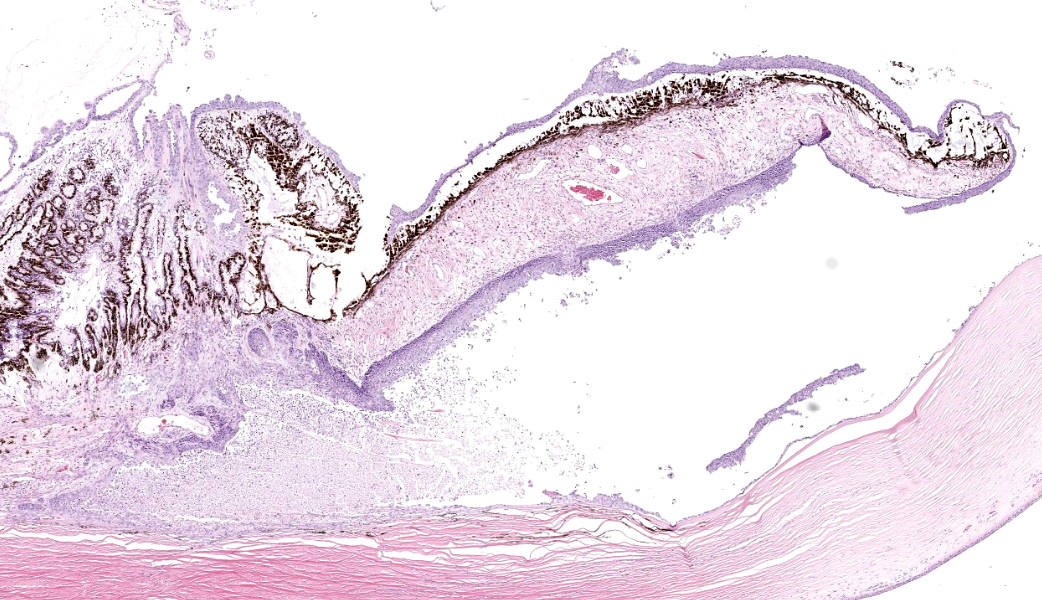

Eye: Overlying the corneal endothelium, anterior and posterior iris, portions of the lens epithelium, and the inner surface of the retina, as well as effacing and replacing the ciliary body, and occluding the drainage angle is an unencapsulated, densely cellular, infiltrative, neoplasm composed of epithelial cells arranged in broad dense cords on a moderate fibrovascular stroma. Neoplastic cells are polygonal with distinct cell borders, pronounced intercellular bridging, a moderate amount of pale eosinophilic cytoplasm, and irregularly round to vesiculate nuclei, with up to three distinct nucleoli. Anisocytosis and anisokaryosis is moderate. The mitotic rate is high with up to 12 mitotic figures per ten 40x HPF. Multifocally, neoplastic cells exhibit squamous differentiation. Near the optic nerve, the neoplastic cells invade the vascular and fibrous tunics, elevating and dissecting beneath the retinal pigment epithelium under a detached and coiled degenerate retina. At the caudal interior surface of the globe, there are numerous neutrophils admixed with abundant eosinophilic cellular and karyorrhectic debris and neoplastic cells infiltrate into the retinal vasculature.Contributor's Morphologic Diagnoses:

This case contributor gives a thorough review of intraocular neoplasms in cats, touching on many major points of discussion during review of this case. Conference participants were readily able to reach a diagnosis of metastatic carcinoma, but not all were convinced that this was a metastatic squamous cell carcinoma (SCC) due to the lack of dyskeratosis within neoplastic epithelial cells, coupled with the lack of a primary mass found during workup. The prominent intercellular bridging between the neoplastic cells was noted by all, which can be a major feature of SCC; and squamous cell carcinomas are common tumors of the feline head; however other participants felt strongly that they could not rule out a carcinoma of other origin based on histology alone. For this reason, a morphologic diagnosis of “metastatic carcinoma” was ultimately favored by participants in this case due to the lack of clear-cut evidence of a squamous cell carcinoma on the H&E.There was no argument to be found on whether this was primary or metastatic, as the histologic evidence was strongly supportive of a metastatic process (i.e., the neoplasm primarily found within the highly vascular choroid and uvea, intravascular neoplastic cell emboli, etc.). The secondary changes in the eye were also discussed and it was concluded that this eye had glaucoma secondary to the neoplasm, evidenced by the retinal ganglion cell degeneration and loss with tapetal sparing, occlusion of the drainage angles by both the neoplasm and inflammation, buphthalmia (enlarged globe, attenuated and degenerative corneal epithelium, scleral thinning), and perivascular edema of the aqueous veins that drain the trabecular meshwork of the drainage angle.